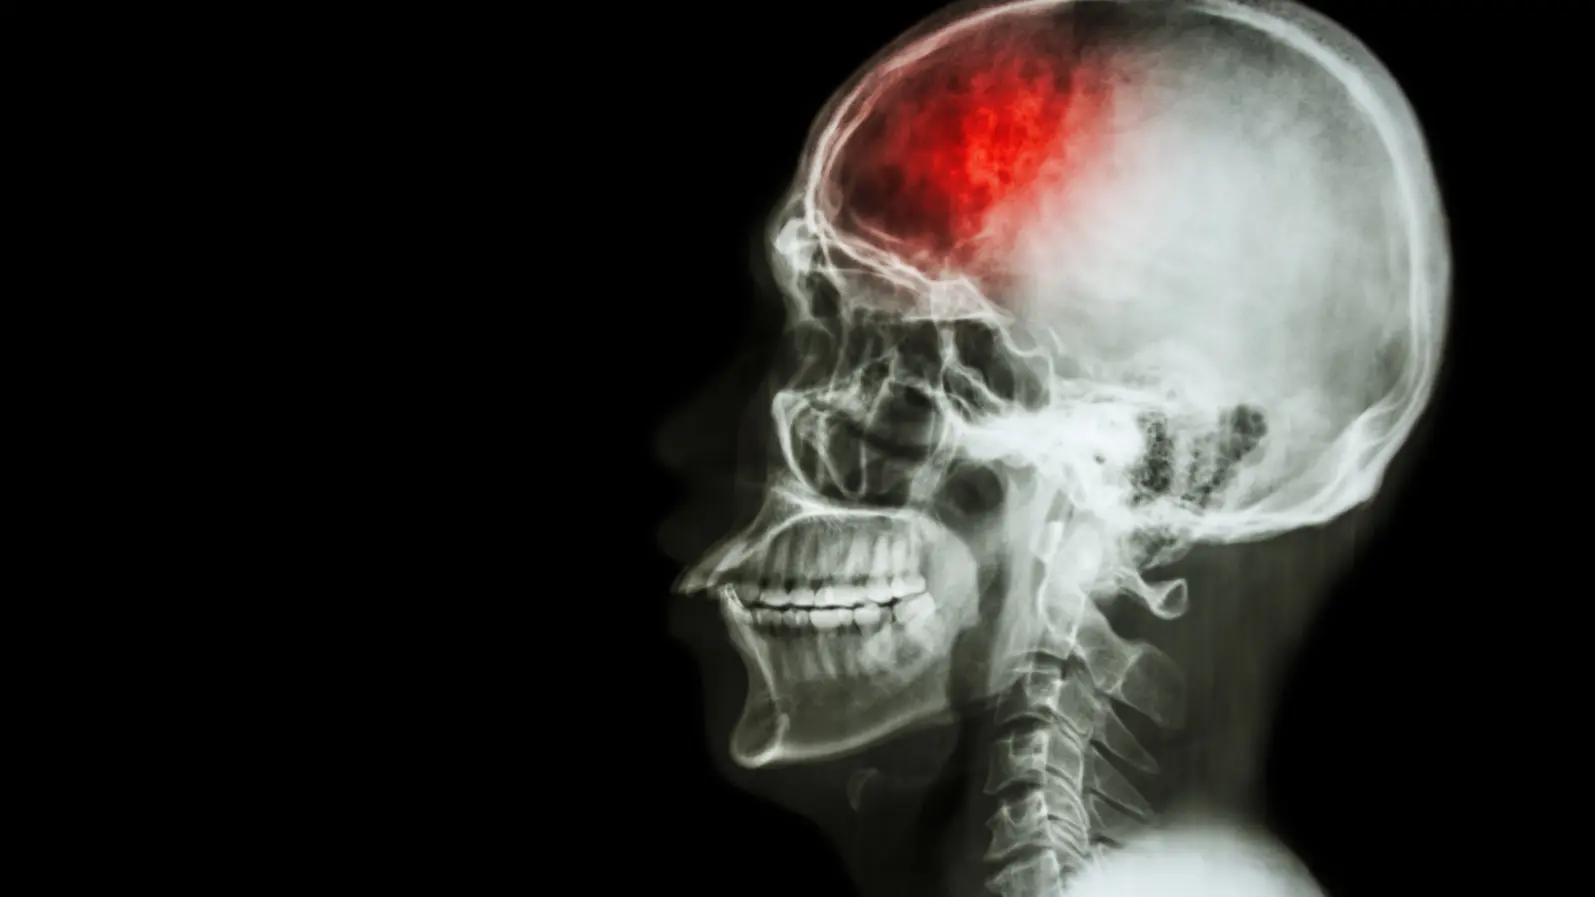

A large U.S. study published in Neurology Open Access has found that people who suffer from both periodontal disease (gum disease) and dental caries (tooth decay) face a significantly higher risk of ischemic stroke — a type of stroke caused by blocked blood flow to the brain.

Interestingly, the highest risks appeared for thrombotic and cardioembolic strokes, which are caused by blood clots or heart-originated blockages.